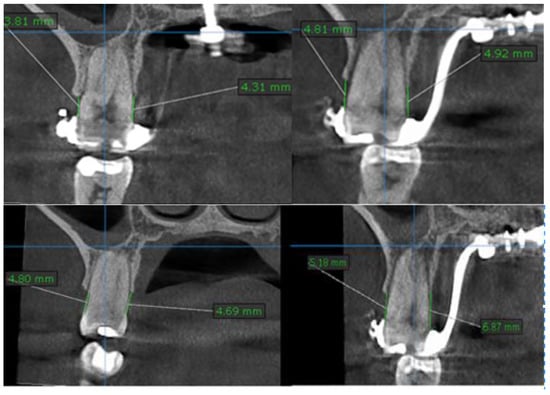

| Molar Bone Level Before Treatment | Molar Bone Level after Split | |

|---|---|---|

| Number of values | 30 | 30 |

| Minimum | 1.97 | 3.67 |

| 25% Percentile | 2.25 | 3.78 |

| Median | 2.2 | 3.995 |

| 75% Percentile | 4.165 | 2.385 |

| Maximum | 4.54 | 6.11 |

| Mean | 1.056 | 3.125 |

| Std. Deviation | 0.3956 | 0.407 |

| Std. Error of Mean | 0.1108 | 0.09102 |

| Lower 95% CI of mean | 1.534 | 2.934 |

| Upper 95% CI of mean | 1.998 | 3.316 |